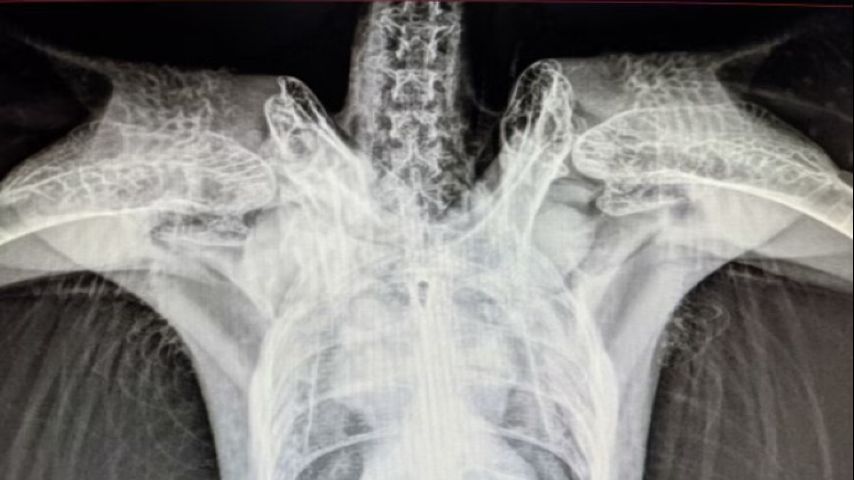

Veterinarians confirmed that she'd sustained shoulder injuries and radiographs revealed that she had fractures to her right clavicular and coracoid.

The coracoid is a bone that connects the cranial edge of the sternum to the shoulder joint. It is fractured or luxated most often when the bird has a frontal collision with an object.

The fracture was diagnosed when radiographs were taken.